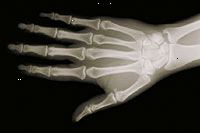

X-paprsky, jsou vyrobeny s použitím externího záření produkovat obrazy těla, jeho orgánů a dalších vnitřních struktur pro diagnostické účely. X-paprsky procházejí tělesných struktur na speciálně ošetřené desky (podobně jako fotoaparát filmu) nebo digitálních médií a "negativní" typu obrázek je (pevnější konstrukce je bělejší, že se na filmu).

Když tělo prochází rentgeny, různé části těla, aby různé množství rentgenových paprsků projít. Měkkých tkání v těle (např. krev, kůži, tuku a svalů), aby většina z X-ray projít a objevují tmavě šedá na film nebo digitální média. Kosti nebo nádor, který je hustší než měkkých tkání, umožňuje několik rentgenů projít a zobrazí se bílá na X-ray. Při přerušení v kosti, X-ray paprsek prochází rozbité oblasti a jeví se jako tmavé čáry na bílé kosti.